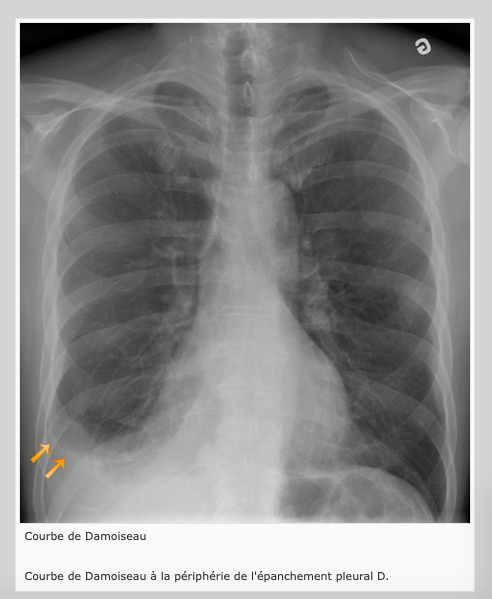

Épanchement pleural

Émoussement des culs-de-sac costo-diaphragmatiques (épanchement pleural)